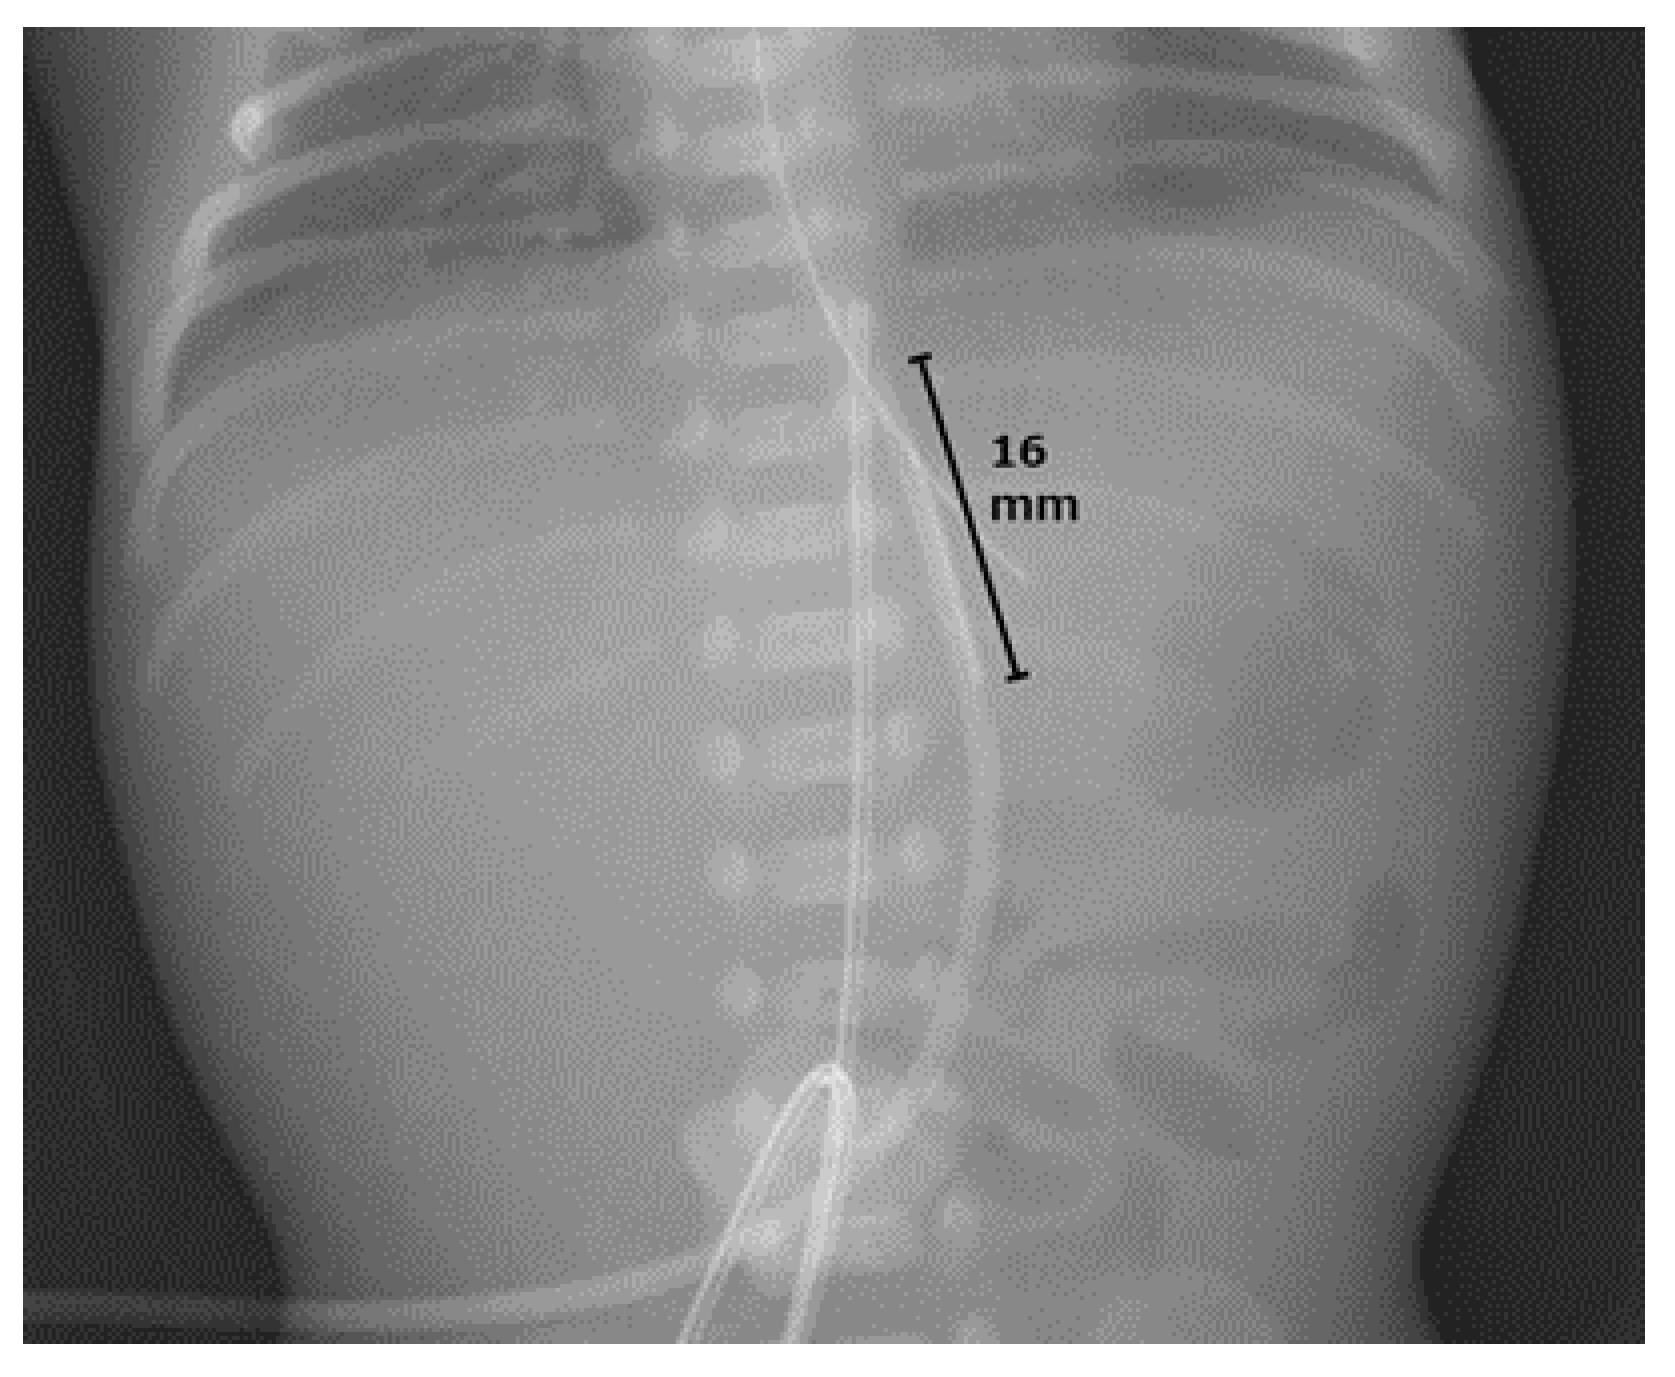

2. Case Presentation